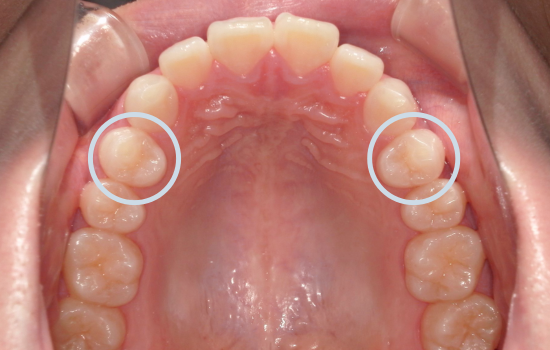

<初診時>

一見すると大きなガタガタはなく、歯並び自体は比較的きれいに整っているように見えます。

角度を変えて確認すると、上の前歯が前方に突出しており、上下の前歯がしっかり噛み合っていない状態(前歯部に隙間)が認められました。

このように、歯列の乱れは軽度である一方、前歯の前突および口元の突出感が認められました。

「口元をしっかり引っ込める」ためには、前歯を十分に後方へ移動させる必要があります。今回は、上下左右の第一小臼歯(4番)を抜歯しました。

この抜歯によってできたスペースを利用し、前歯を後方へ引き下げていきます。